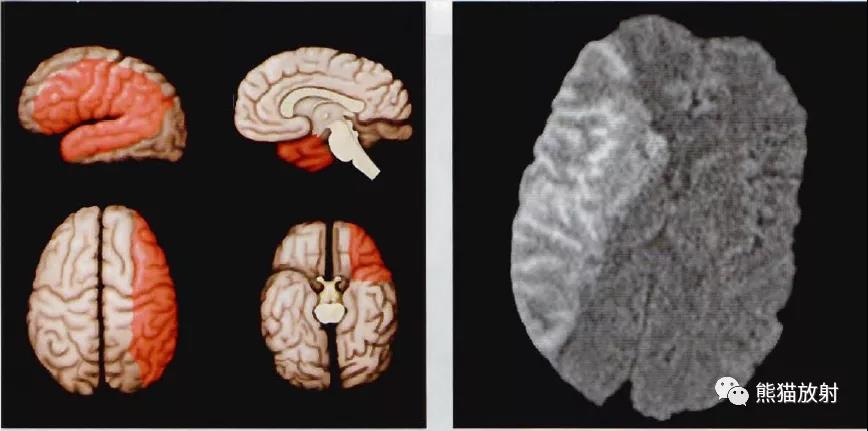

(左)示意图绿色区代表ACA皮质血管分布区。ACA供应大脑半球内侧前2/3区,大脑凸面的分布范围存在变异。胼胝体通常也是主要由ACA分支供血:胼胝体穿通动脉、胼胝体周动脉和后膝部分支动脉。

(右)轴位NECT显示左侧ACA分布区额叶内侧镰旁低密度(箭),系亚急性梗死改变。

(左)示意图显示红色区代表MCA皮质血管分布区。MCA主要供应大脑半球外表面,包括额叶、颞叶和顶叶。另外,多数豆纹动脉起源于M1段、供应基底节区。

(右) 轴位DTI trace成像显示右侧MCA分布区弥散受限。累及基底节表明血管闭塞发生在豆纹动脉近端。